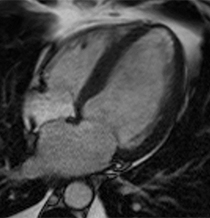

Image of a heart with dilated cardiomyopathy

- MRI of the heart.